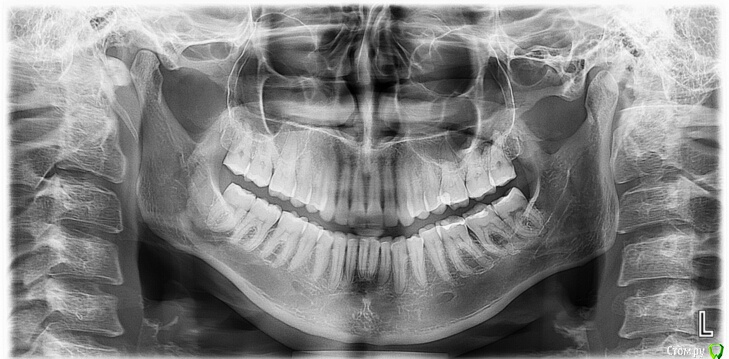

Стираемость слева

Слева стираемость зубов.

Три месяца назад пролечили 36 зуб по среднему кариесу, есть им не могу (заводила тему).

Поэтому увеличилась нагрузка на правую сторону челюсти. Начались небольшие щелчки. Вторую неделю затылок тянет, голова побаливает и щётки с утра чуть сильнее.

Два врача (ортодонт и стом.терапевт) шлифавнуть зубы справа, но мне как-то не хочется снимать эмаль(